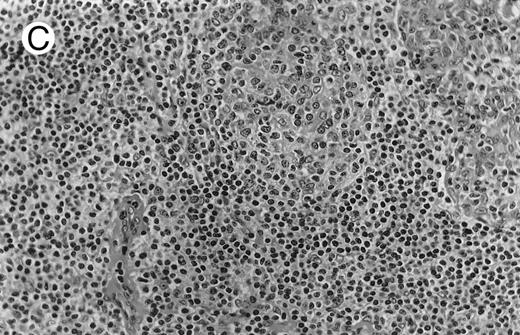

Low-grade marginal zone B-cell lymphoma (MZL; REAL classification)9 comprised the largest number of cases (n = 12). Nine of them were low-grade MALT type lymphomas involving parotid, stomach, bronchus, buccal mucosa, and skin. The histological pattern was relatively homogeneous, showing diffuse lymphoid infiltrates that included small lymphocytes with round nuclei or with plasma-cell differentiation and/or centrocyte-like cells with indented nuclei (Fig 1A). Lymphoepithelial lesions were observed in each case, regardless of the tissue involved (Fig 1B). Monocytoid cells characterized by a larger cytoplasm and a slightly irregular nucleus were mixed with centrocyte-like cells in 2 cases of MALT lymphoma arising in the parotid (cases no. 3 and 15). There were also scattered occasional large cells (centroblast or immunoblast). In cases no. 3, 6, and 15, remnants of germinal centers with partial follicular colonization were observed (Fig 1C). Beside these 9 low-grade-type mucosal lymphomas, 3 nodal lymphomas (cases no. 8, 10, and 14) had histological features similar to that of low-grade MALT type lymphoma because they showed a typical lymphoplasmacytoid infiltration with a variable proportion of blasts. In 2 cases, the presence of numerous immunoblasts or centroblasts, mixed with small lymphoplasmacytoid cells or plasma cells, indicated an evolution to a more aggressive lymphoma (Fig 1D). The third nodal lymphoma showed a small lymphocytic or lymphoplasmacytoid diffuse infiltrate associated with intrasinusal large nests of monocytoid cells. This histological picture is characteristic of monocytoid B-cell lymphoma (MBLC; Fig 1E).

(D) Case no. 10. Immunocytoma in lymph node. The infiltrate is composed of small lymphocytes, plasma cells and blasts. (E) Case no. 14. Monocytoid B-cell lymphoma in a cervical lymph node with a monocytoid component located in dilated sinuses.